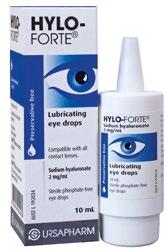

Hylo-Forte® Eye Drops 10mL $3499 Designed to provide effective relief from dry eye and other related eye conditions. Opti-Soothe® Moist Heat Mask $1999 $1499 from Bausch + Lomb Renu Fresh Duo $1999 Proven to fight germs, clean lenses, and remove irritating protein deposits daily from your soft contact lenses for that fresh lens feeling every day. HIGH QUALITY, GREAT VALUE LENS SOLUTION Radiant Health Ltd, Auckland. Offers and advertised products may not be available at all participating pharmacies. Offers are valid from Monday 6 March to Friday 24 March 2023 or while stocks last. Prices printed in this brochure are Recommended Retail Prices (RRP). Always read the label. Use only as directed. If symptoms persist see your doctor or health professional. Vitamins are supplementary to a balanced diet. Full product information is available from your pharmacy TAPS PP9728. EVERYDAY ESSENTIALS

Preservative-free

lubricant

film

designed

of

Lubricating eye drops for intensive lubrication of the eye, in eyes that are experiencing severe or persistent dryness.